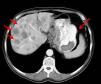

La existencia de las áreas de necrosis y la edad del paciente orientaron hacia el origen paraneoplásico de la DM. Una tomografía axial computarizada reveló la existencia de un cáncer gástrico con metástasis hepáticas (fig. 2). El paciente recibió tratamiento quimioterápico que incluyó 5-fluorouracilo, antraciclinas y cisplatino; con él se redujo la masa tumoral y se resolvieron las lesiones cutáneas.